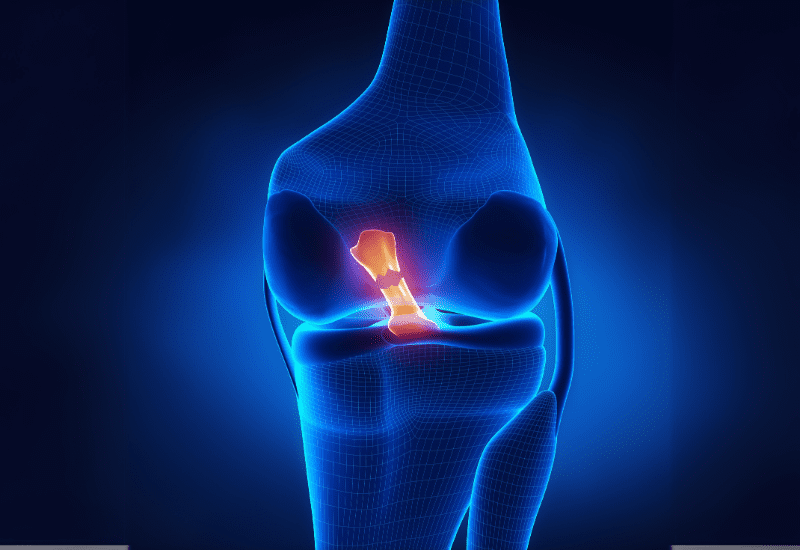

Desgarro de meniscos

El menisco actúa como amortiguador entre el fémur y la tibia.

Al girar la pierna con el pie fijo, puede desgarrarse, provocando dolor al rotar o al agacharte.

- Ecografía: para diagnóstico de bursitis o desgarros meniscales.

- Resonancia magnética: para visualizar ligamentos, meniscos y tejidos blandos.